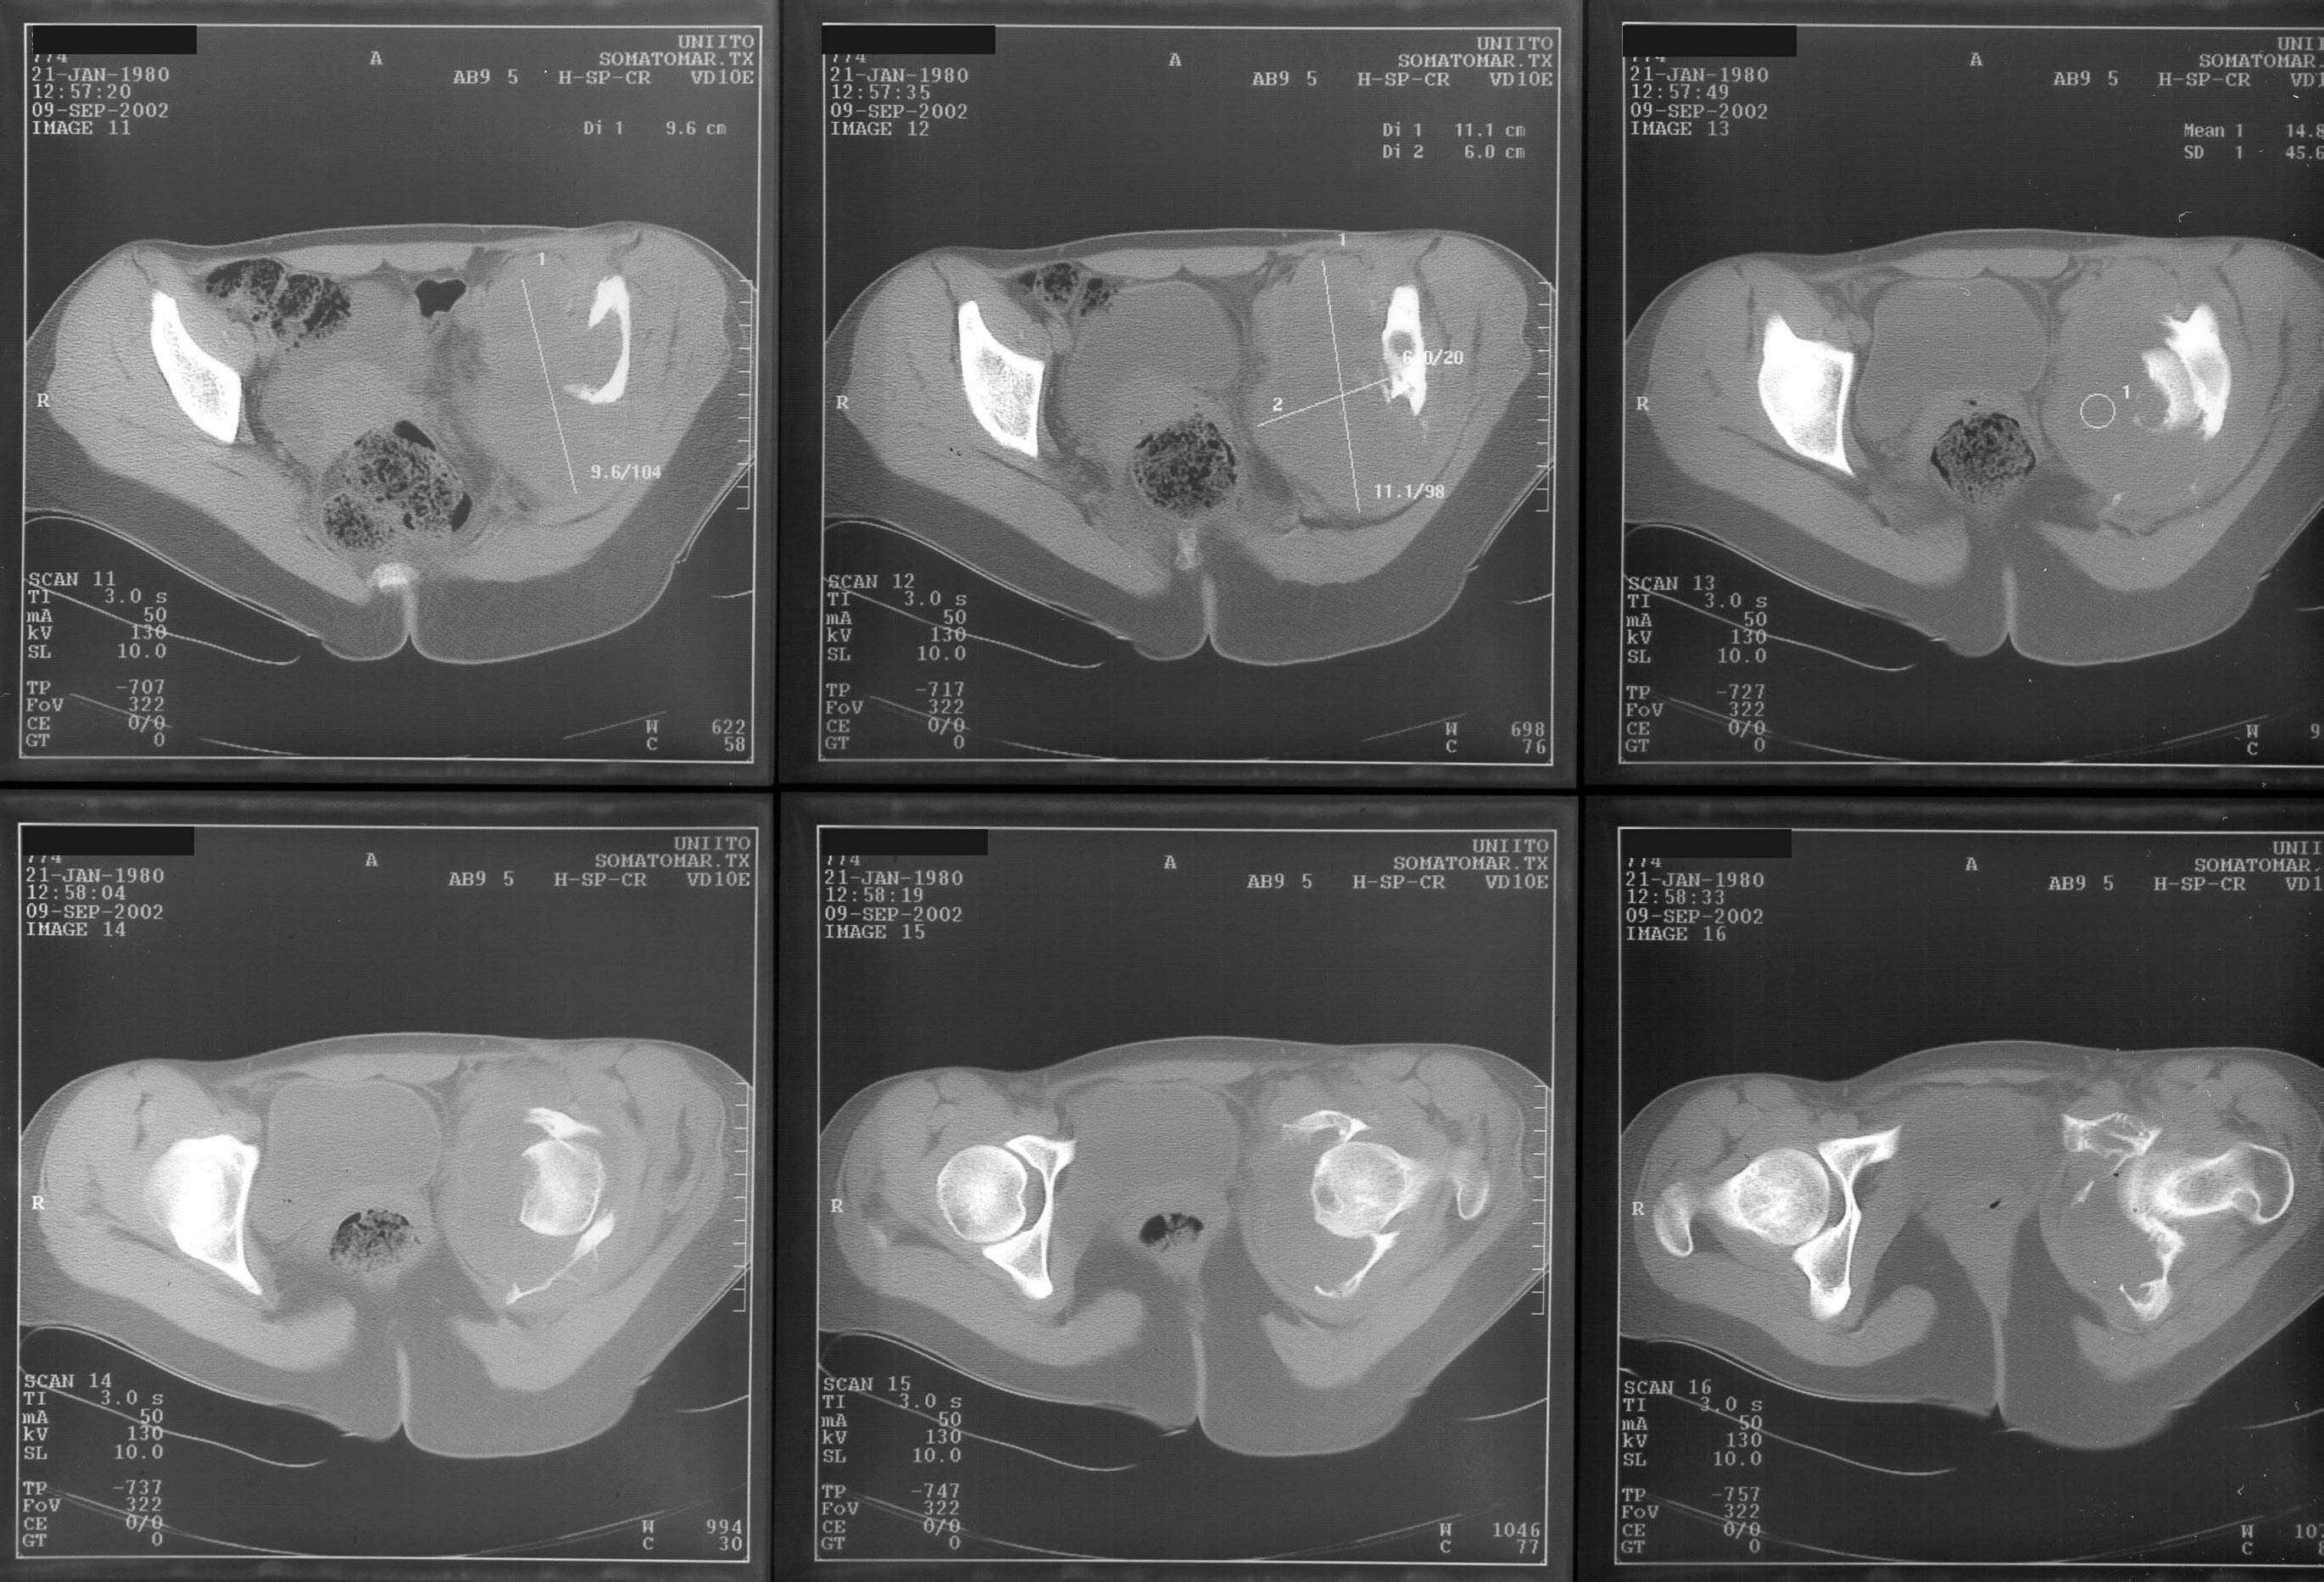

A female 22 years old admitted with the hip protrusion. Xrays are 12 months apart. Biopsy doesn't confirm malignization. What surgery can be done here? Is there any chance of primary hip replacement?

I think you need to get the opinion of a musculoskeletal oncologist, but it appears that this patient has an aggressive giant cell tumor and will likely require an aggressive wide excision. As a result reconstruction will be difficult.